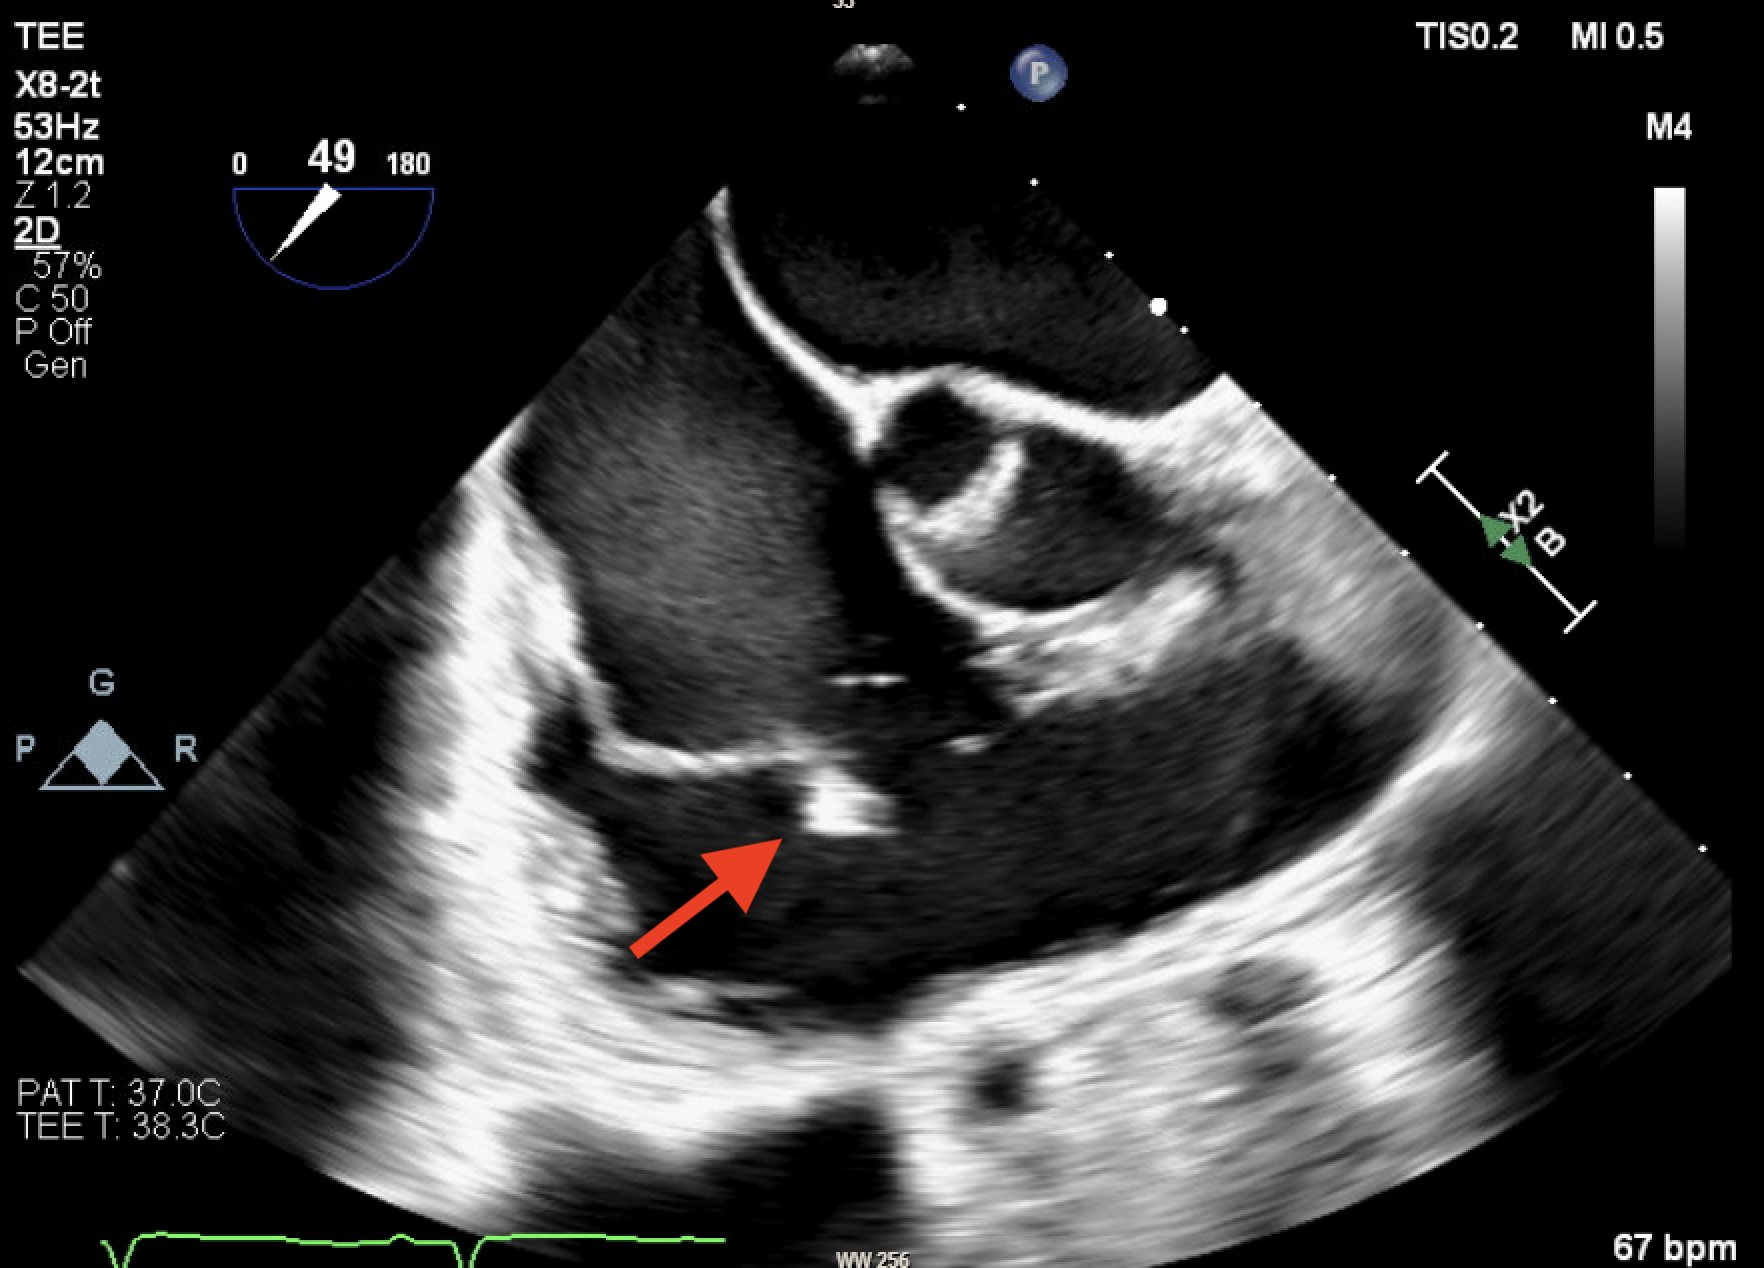

33-year-old female with a history of polysubstance IV drug abuse, hepatitis C infection, multiple hip surgeries with abscess drainage, tricuspid valve endocarditis with MRSA bacteremia, treated with IV Ceftaroline and daptomycin for 6 weeks via left PICC line, which was removed 2 weeks before her hospital presentation. The patient presented to the hospital with complaints of fever and generalized weakness, she was treated with broad-spectrum antibiotics, and investigations with TEE revealed mobile Tricuspid valve vegetation as well as a linear, highly mobile, tubular structure within the SVC extending into the right atrium, presenting a GFCS. CT chest also revealed multiple septic emboli, and blood cultures were positive for Serratia marcescens and ESBL Klebsiella pneumoniae. Patient was started on Anticoagulation with Eliquis and was evaluated by the Cardiothoracic surgery team for possible AngioVac, yet no good targets were found, and a decision was made to treat the patient medically without placing any further central lines. Unfortunately patient had signed out AMA after 1 week before completing her antibiotics course, yet she continued to take Eliquis outpatient. Patient returned to our Center 2 months later with similar complaints, TTE revealed large 3.8 * 2.35 cm highly mobile, irregularly shaped Tricuspid Valve mass that has significantly increased in size in comparison with prior imaging, and complete resolution of the previosly seen GFCS, Patient again left AMA refusing further treatments and investigations.

Ghost fibrin catheter sheath (GFCS) is a rare condition that can sometimes be a harmless incidental finding. However, it may also pose a risk of thrombosis and embolization, particularly in the context of infective endocarditis. While definitive treatment guidelines are lacking, antibiotics and anticoagulation are commonly used. AngioVac has been used in some instances, but its clear benefits has not been established. Our case demonstrated complete resolution of the GFCS with anticoagulation despite not being compliant with antibiotics.